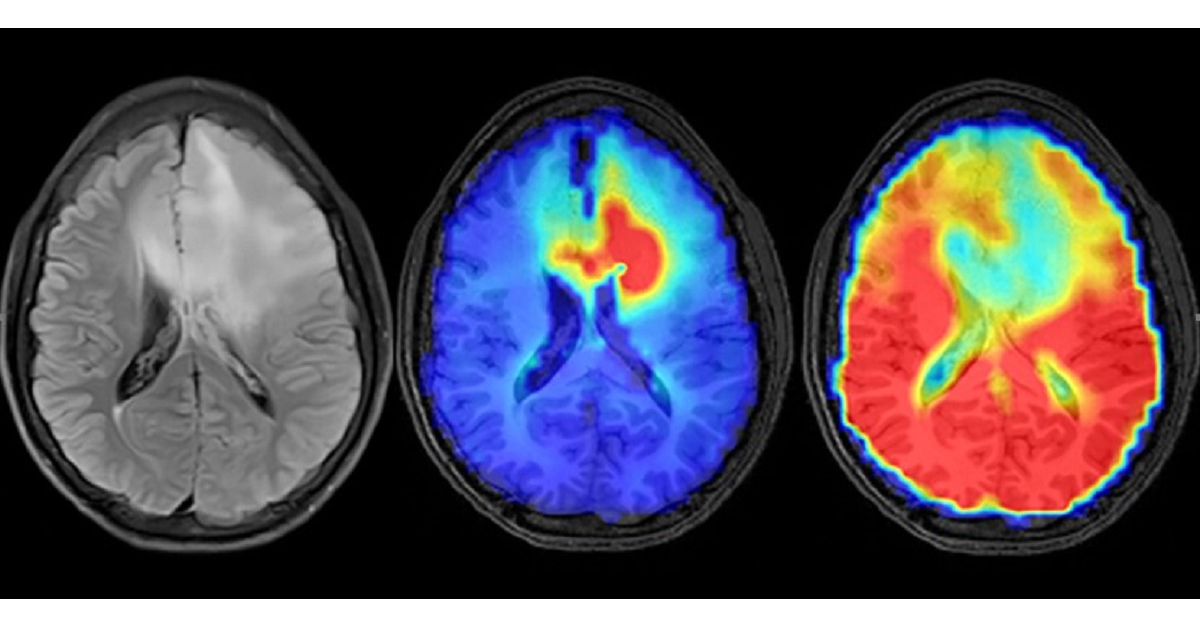

Radiation therapy plays a crucial role in managing both benign and malignant brain tumors. Recent advances in imaging and radiation delivery have expanded the use of radiation therapy and significantly improved patient outcomes. Advanced imaging techniques such as magnetic resonance imaging (MRI) utilizing three-dimensional spectroscopy and perfusion have enhanced the delineation of gliomas, allowing for more precise treatment planning and assessment of the treatment response. Furthermore, new radiation delivery techniques such as IMRT, stereotactic radiosurgery, and proton therapy have enabled more accurate targeting of tumors while minimizing damage to surrounding healthy tissue. These advancements have resulted in improved treatment outcomes and enhanced quality of life for patients with brain and spine tumors.

This series of articles will focus on recent breakthroughs in tumor imaging and radiation therapy for brain and spine tumors. The articles will cover various topics, including the role of functional imaging in treatment planning, the effectiveness of immunotherapy in combination with radiation therapy, and the potential of radiomics in predicting the treatment response. These articles will provide insights into the current state-of-the-art in radiation therapy for brain and spine tumors and offer valuable information for clinicians involved in managing these patients.